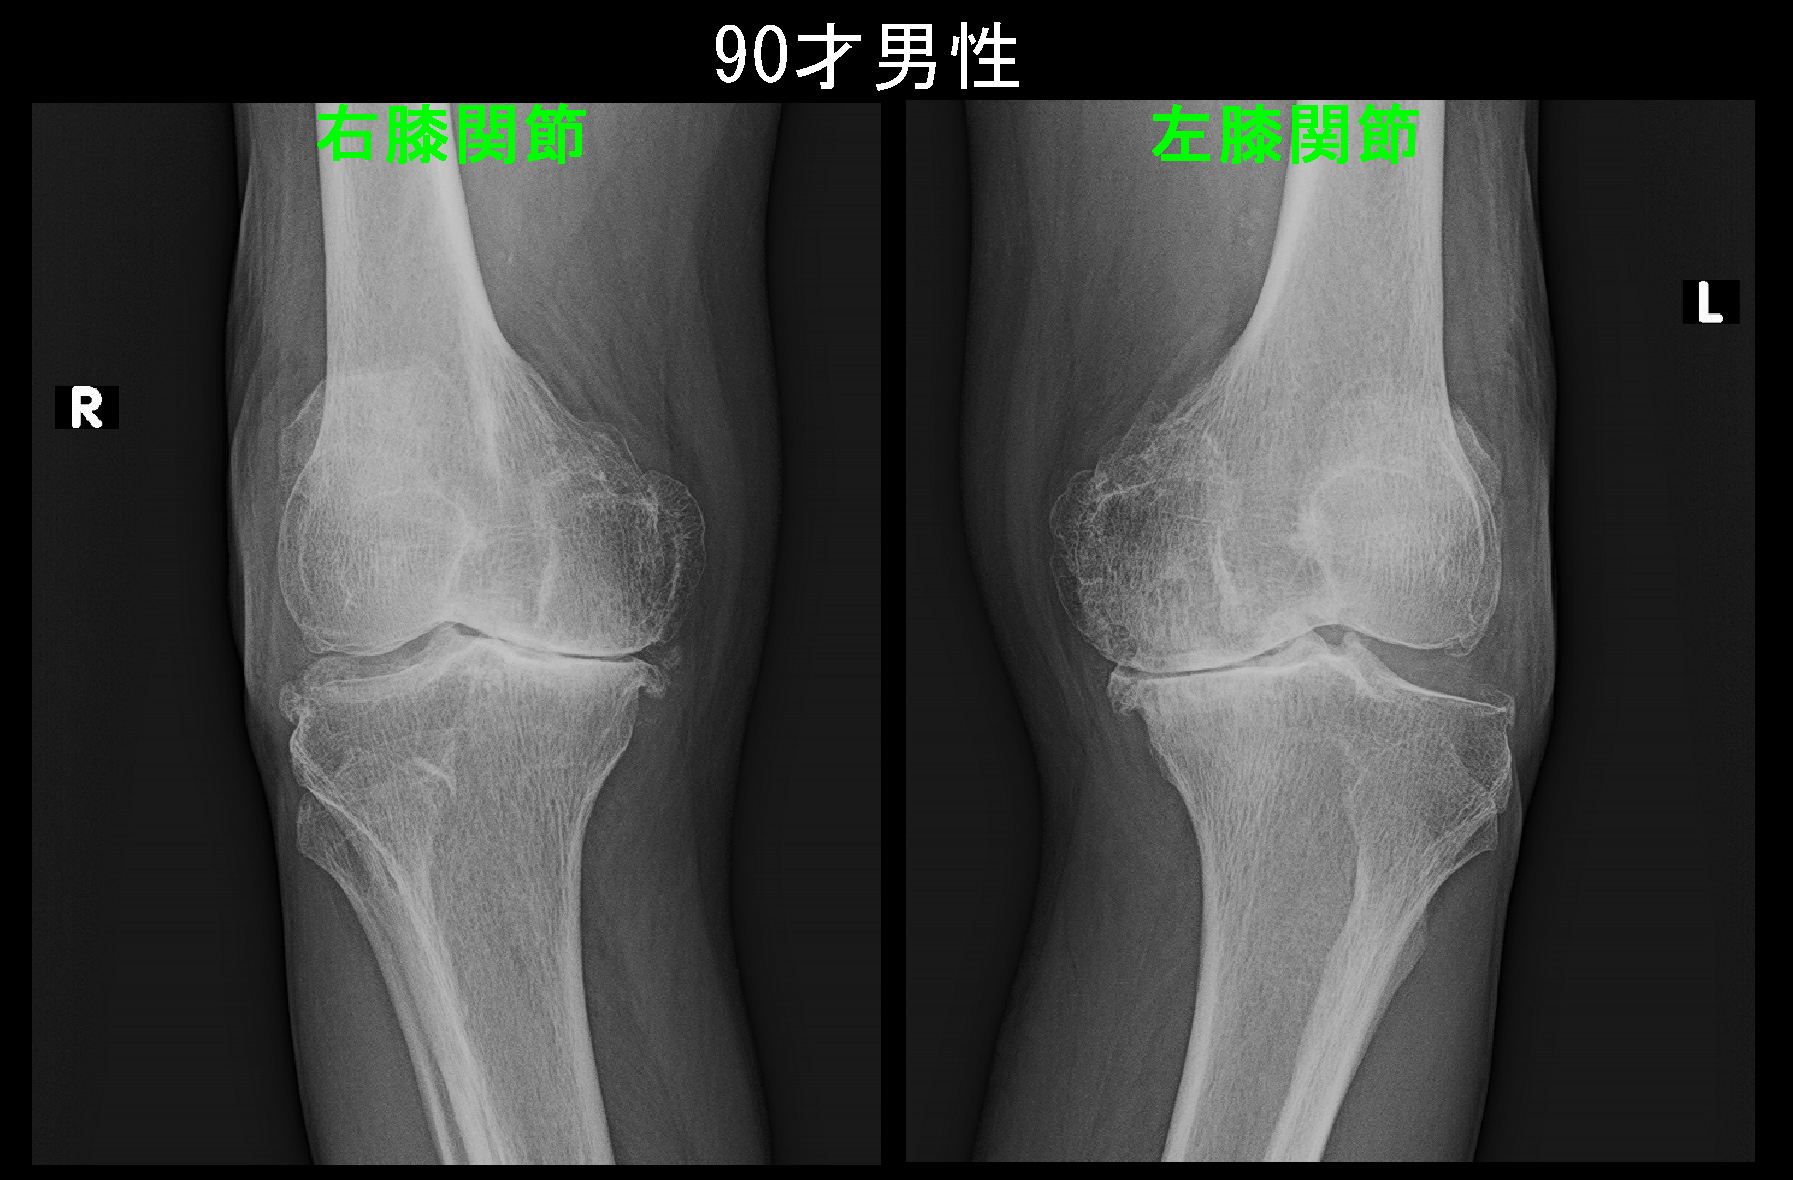

もう1人、ほぼ同じ期間変形性膝関節症の保存的治療を継続していた患者さんの左膝のレントゲン像を提示したいと思います。

70才の果樹と野菜を作っている農家の男性です。先の77才の女性の患者さんが手術を希望された翌日の令和3年9月25日に月1回の定期的な受診をされました。

70才男 Xp.jpg

この患者さんは5年前の平成28年12月16日に左膝痛で当院を受診され、中等度の左変形性膝症に対して投薬とともに月1回のヒアルロン酸製剤関節内注入療法を継続してきました。左膝の内側の関節裂隙は5年の経過で軽度狭くなっていますが(オレンジ矢印と赤矢印)、5年の経過で先の77才女性の患者さんのように関節裂隙が消失し、骨まで摩耗して崩れるというような印象は全くありません。投薬は痛みを軽減するための対症療法でしかなく、関節軟骨の摩耗の予防はヒアルロン酸製剤によっているわけですが、十分な治療効果が表れていると理解して良いと思われます。

ヒアルロン酸製剤関節内注入療法による関節軟骨の摩耗予防と服薬による痛みの軽減を図りながら、患者さんの膝の老化の進行が停止して、生活状態で過剰な負担が膝にかからなくなれば膝痛は一定軽減し、落ち着く可能性があります。